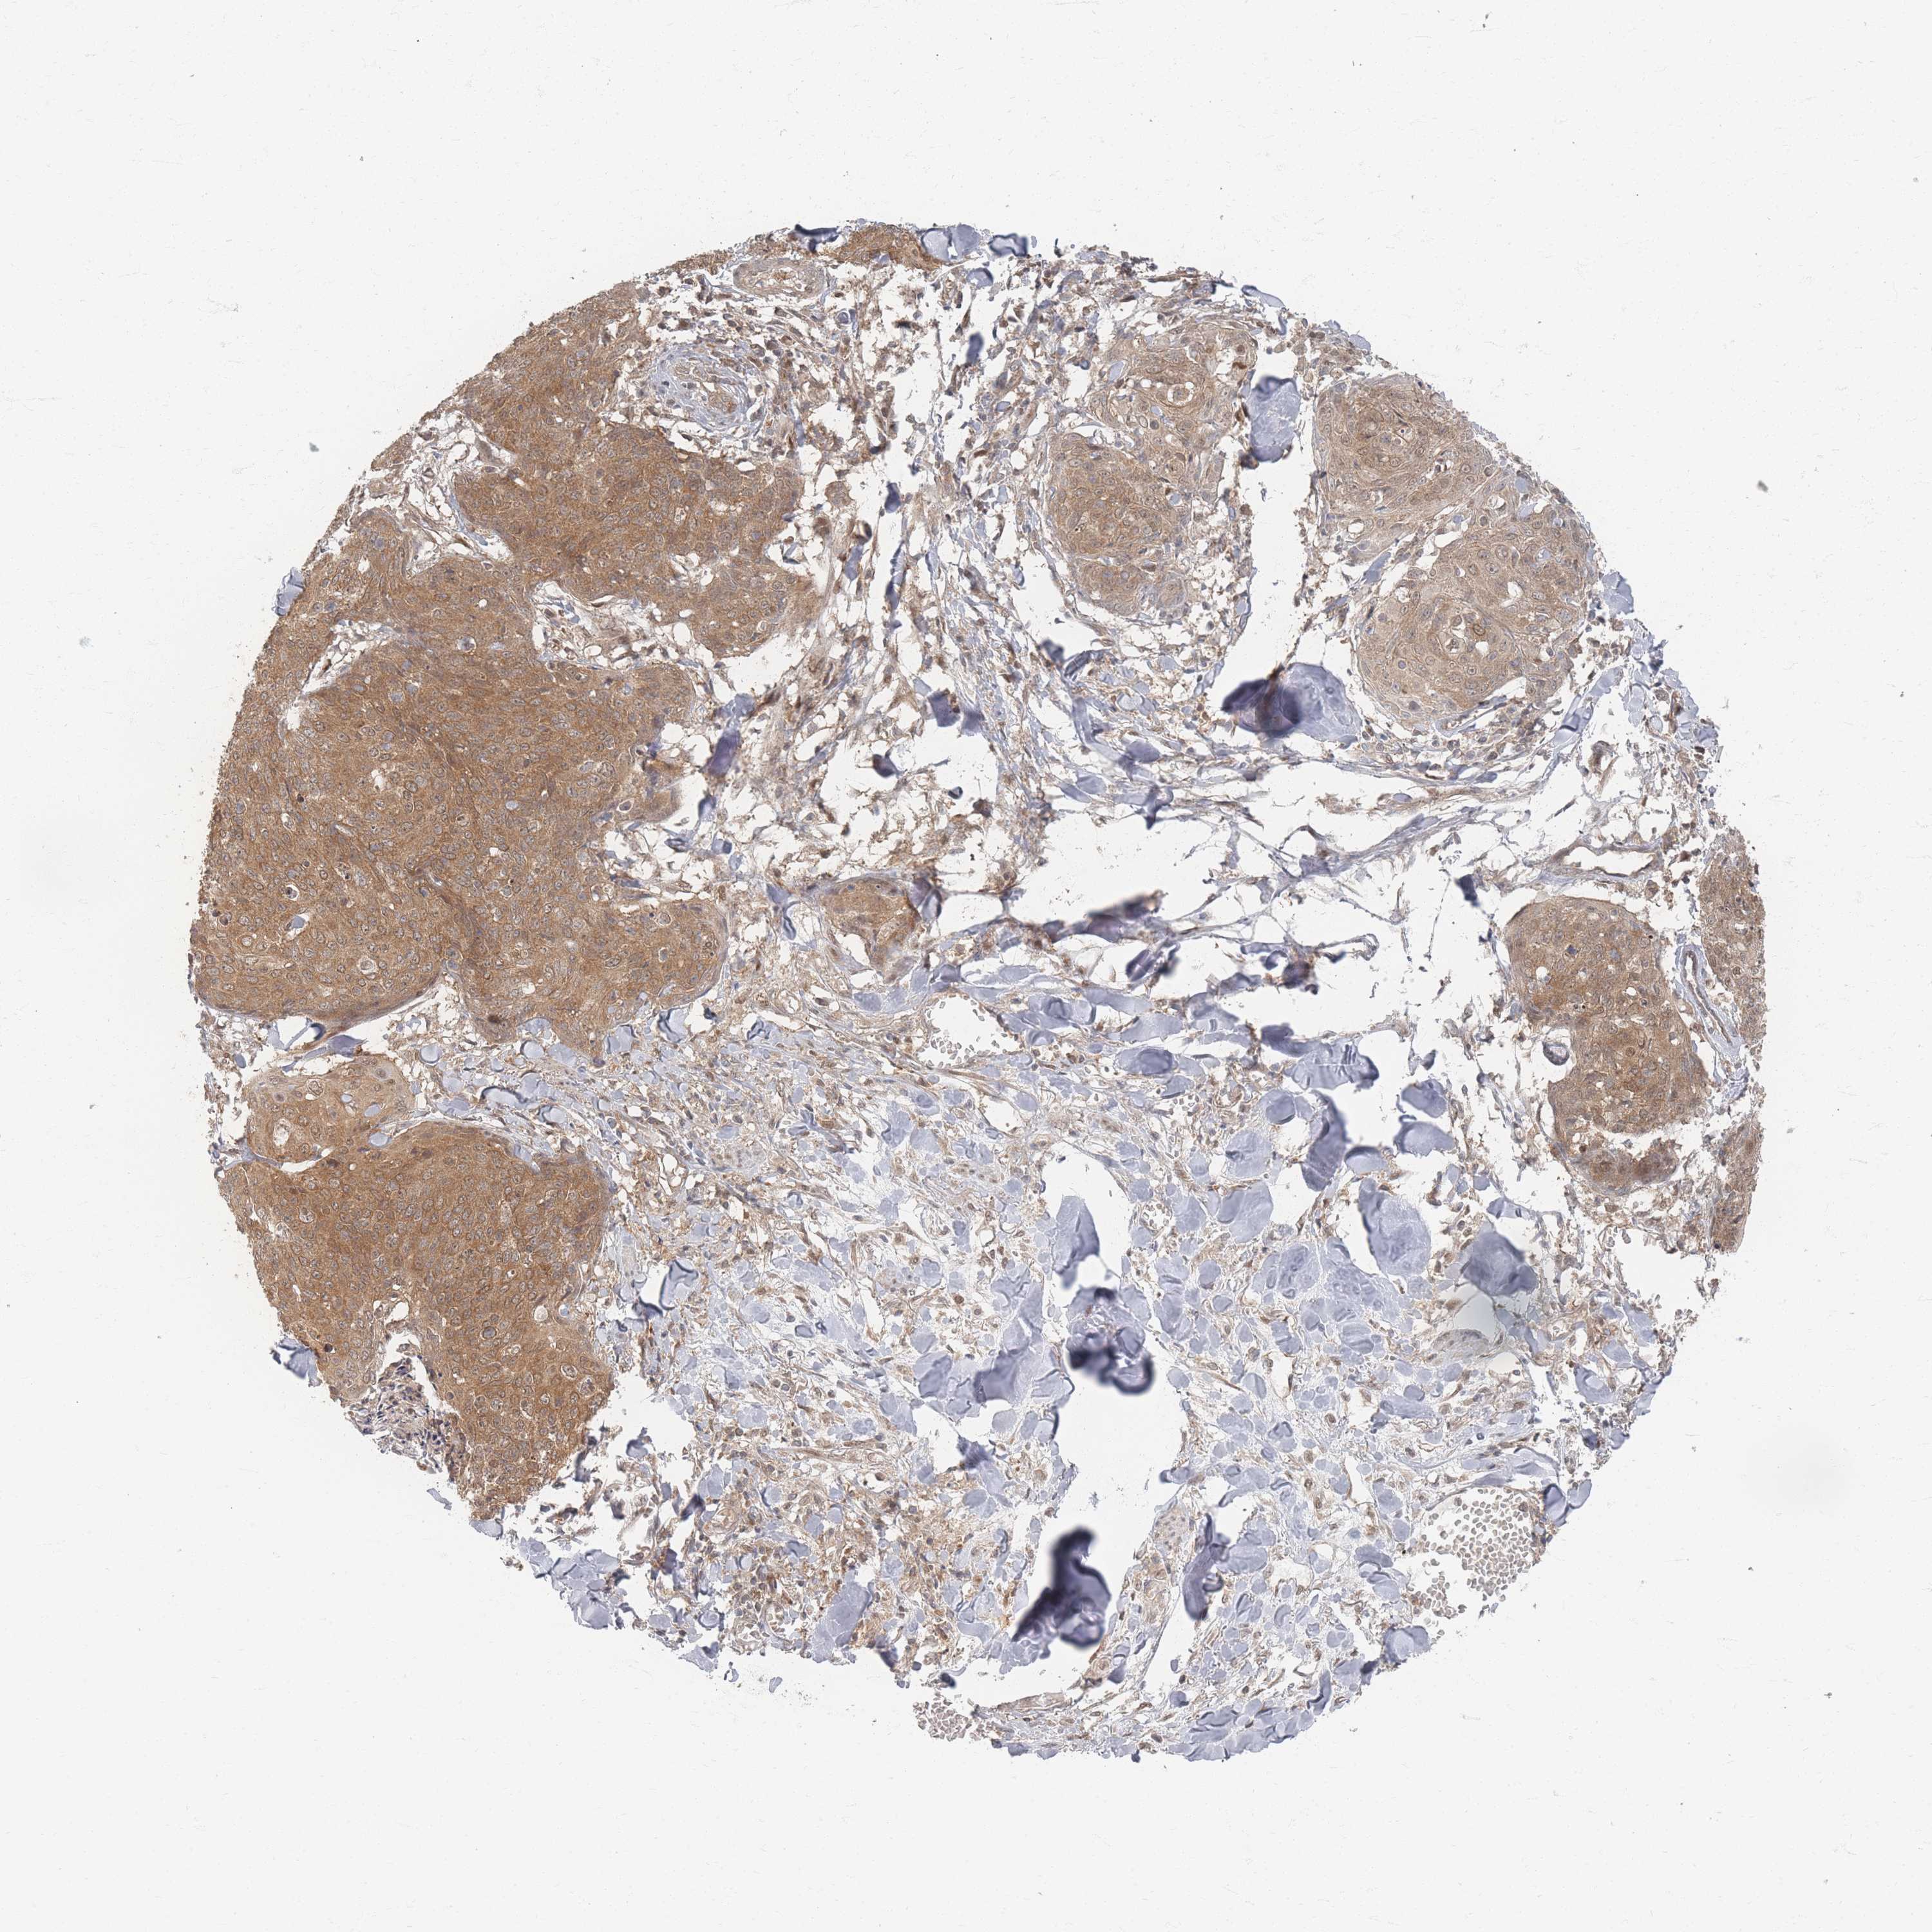

CANCER SKIN CANCER Show tissue menu

Basal cell and squamous cell cancer

SKIN CANCER - Protein expressioni

A mouse-over function shows sample information and annotation data. Click on an image to view it in a full screen mode. Samples can be filtered based on level of antibody staining by selecting one or several of the following categories: high, medium, low and not detected. The assay and annotation is described here.

Each image is clickable and will lead to virtual microscopy that enables deeper exploration of all samples and also displays staining intensity scores, fraction scores and subcellular localization as well as patient and tissue information for each sample.

Antibody HPA044220

Squamous cell carcinoma, metastatic, NOS